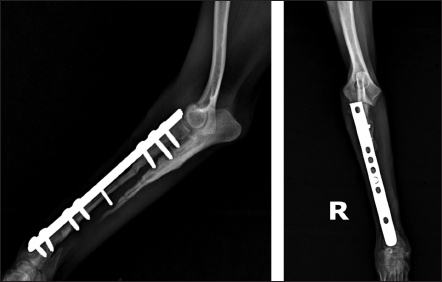

То harvest the autogenous cortical graft, a caudal approach to the contralateral ulnar diaphysis was used (Fig. 2). The subcutaneous tissue was bluntly dissected, and thereafter retraction was maintained using Gelpi retractors. A Hohmann retractor was placed between the ulna and radius to prevent iatrogenic damage to the radius. A 4.8 cm long bone segment of the ulnar diaphysis was removed by means of an oscillating saw. The ostectomy and periosteum were removed en bloc and transferred into the surgical gap of the right radius. At both ends of the cortical autograft, a cancellous graft soaked with 1,000 IU recombinant human erythropoietin (Binocrit®, 2000 IU, Sandoz GmbH, Kundl, Austria) was applied for optimization of osteoinduction and angiogenesis. To collect the cancellous graft, a small incision was made over the craniolateral aspect of the greater trochanter. A 3.5-mm hole in the proximal humeral metaphysis was created with a drill bit and a bone curette was used to harvest the cancellous graft. Then, it was inserted into the recipient site as soon as possible to minimize cell death. After proper alignment of bone fragments, they were fixed with a dynamic compression plate (1.5 mm thickness) and 8 cortical screws: 2 in the distal radial fragment, 3 in the cortical graft, and 3 in the proximal radial fragment (Fig. 3). The intradermal layer was closed with an absorbable monofilament suture material (PDX, 3-0, VetSuture, France), followed by non-absorbable skin sutures (Nylon, 3-0, Kruuse, Denmark).

Fig. 3. Mediolateral radiograph of antebrachial bones after the revision surgery. Left: the ulna of the healthy thoracic limb after harvesting of the cortical autograft. Right: fixation of the cortical autograft with dynamic compression plate.